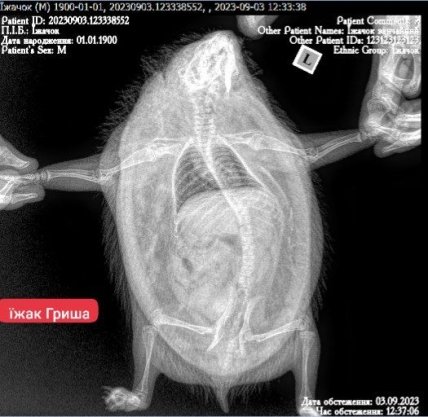

Їжачок на рентгені

Якщо тваринка була травмована, їй, як людині може знадобитись рентген. Якщо хворіють зуби - зоостоматолог